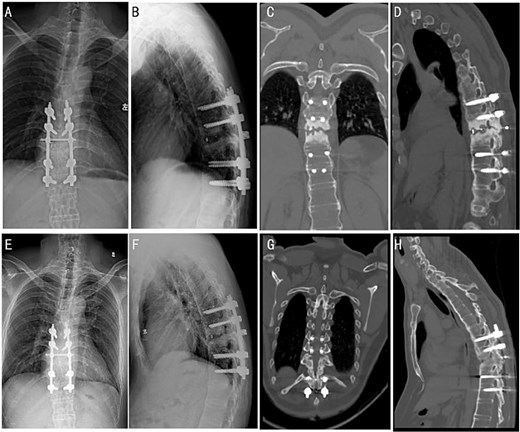

Surgical intervention was performed under general anesthesia. A posterior surgery approach from T8 to T12 was used under intraoperative C-arm fluoroscopy guidance. Pathological analysis of the intervertebral disc tissue confirmed the absence of inflammatory cell infiltration (Fig. 2A–C). Post-operative X-ray and CT imaging confirmed good alignment of the thoracic spine and stable internal fixation (Fig. 2D–I).

(A–C) Intraoperative pathology specimens obtained for further analysis. (D and E) Post-operative full-length spinal X-ray images. Typical post-operative Sagittal (F and G) and 3D CT reconstruction (H and I).